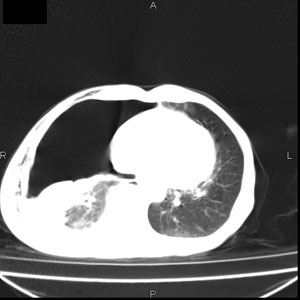

患者男,77岁,于3日前从树上摔下,头部查ct示蛛血,硬膜下出血,上腹部ct未见明显异常,右侧胸腔积液,左侧如常。肺部拍片示右侧肋骨多发骨折住院后今日来查肺部ct,我看到的是1。右侧胸腔血气胸并右肺上叶,中叶压缩性肺不张,2。右肺下叶肺挫伤并多发肋骨骨折,肌内及皮下积气3。左侧少量胸腔积液,我想请教的是3天前左侧胸腔里没有积液今天怎么出现了呢,是什么原因呢?请讨论。

有肺挫裂伤,有渗出,

回复楼主   左侧液气胸,液体来源1、肯定有血液成分,多少不一定。2、胸膜腔渗液,由于肺压缩、活动度下降,肯定胸膜吸收有问题,导致积液增多。

因为3天前病人刚摔的时候,左侧胸腔受伤不严重,故而当时没有胸腔积液,但病人受到这么大的伤害,胸膜腔内的液体动态平衡肯定会受到影响,所以过一段时间后才出现胸腔积液。